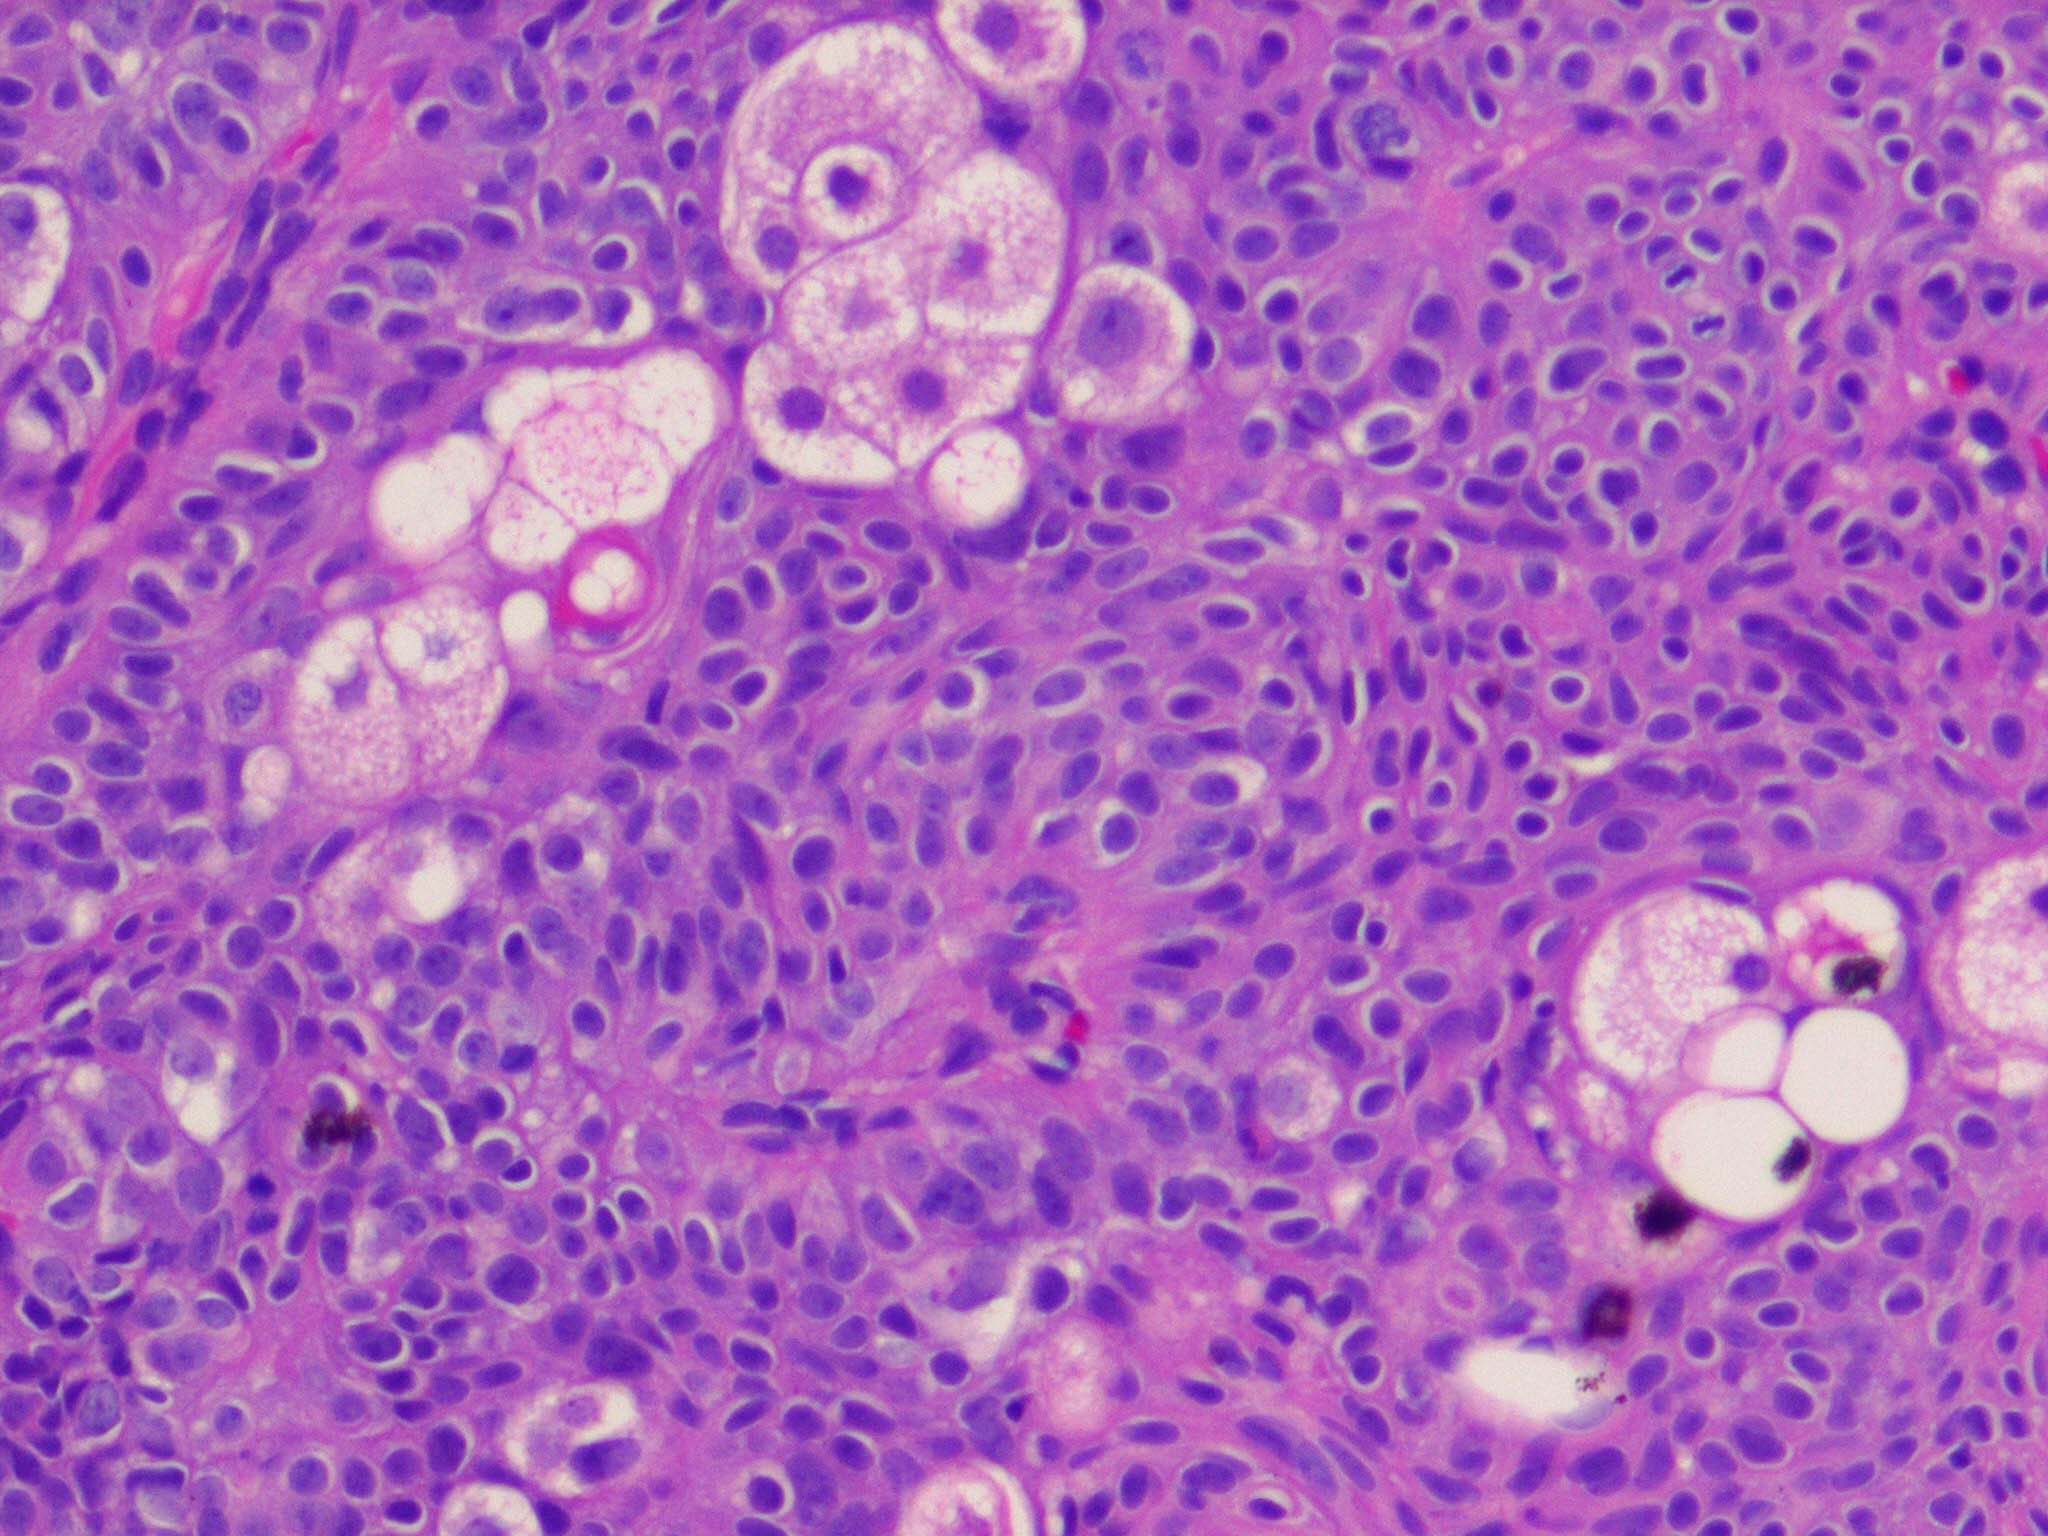

Sebaceous adenoma = غدوم دهني